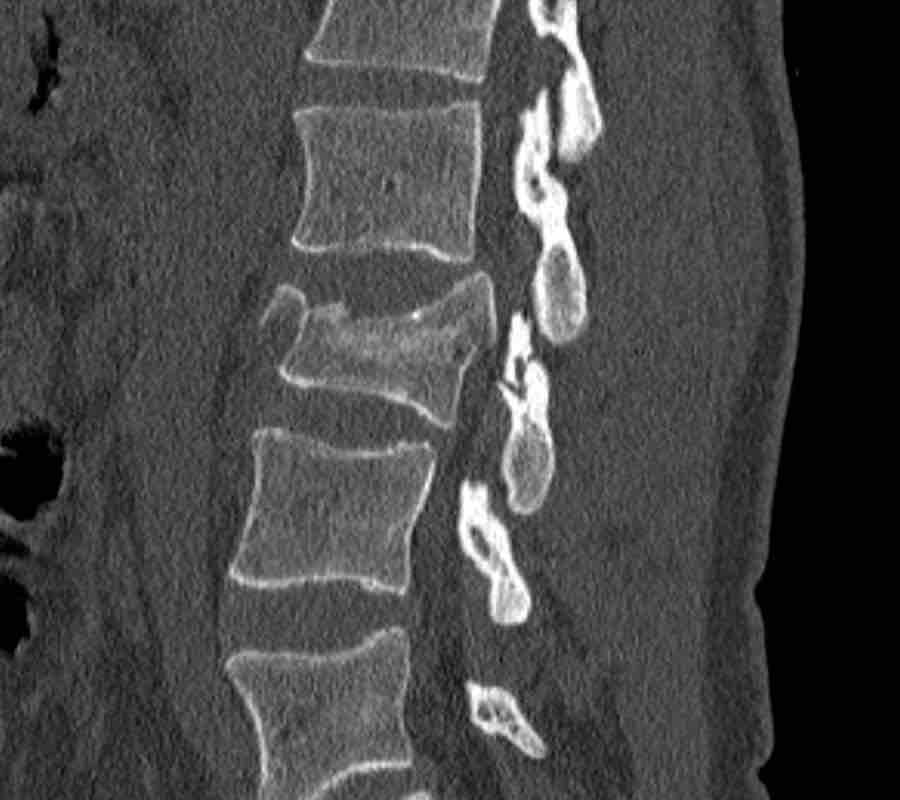

This is a difficult case with injuries at many levels.

What is the most severe level for classification.

Then continue with the second stack below for classification of other levels.

Findings

- The most severe level is L4/5 with dislocation (dotted lines)

- Facet fractures at L4 (arrows).

- A4 burst fracture (circle).

Conclusion:

Injury type C + A4 at L4/5.

Continue with the next stack of images to classify level L2…

Scroll through images.

What is the highest AO-level?

- No dislocation ( no C type).

- Mainly horizontal fractures of spinous processus at multiple levels (B-type).

- Split fracture L2 (type A2).

Conclusion

Injury type B2 + A2 at level L2.